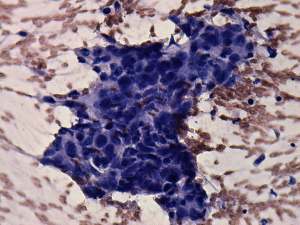

Cytological diagnosis: anaplastic carcinoma.

Histopathology: anaplastic carcinoma.

Comment. The hypothyroidism could cause differential diagnostic problems. The clinical presentation is unequivocal, such tumor must be either anaplastic cancer or MALT-lymphoma. The latter evolves in Hashimoto's thyroiditis and great proportion of the patients have hypothyroidism at the time of diagnosis. Nevertheless, patients with anaplastic cancer may have also hypothyroidism caused by the destruction of the tumor. The frequency of hypothyroidism is around 10-15% in the case of anaplastic cancer. If FNA would not be decisive, the sonographic pattern is be of help: the presence of necrotic foci is a frequent finding in the case of anaplastic cancer but it is a very rare phenomenon in the case of a MALT-type lymphoma.